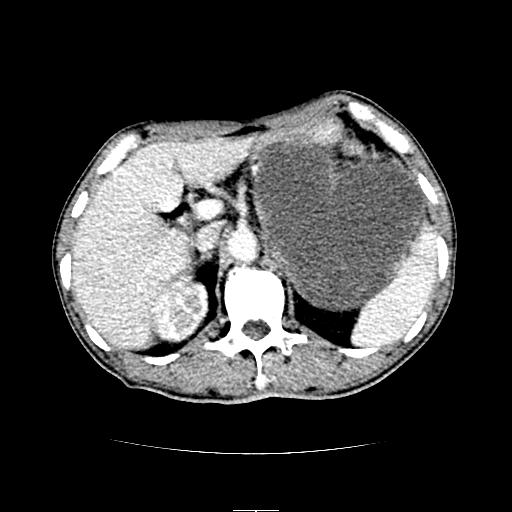

左上腹胃、脾及胰腺间巨大囊性占位性病变,内见多数薄隔,有轻度强化,明显占位效应。左肾见一小囊肿。

考虑:1、左上腹巨大囊肿(可能来源于胰腺)。

左上腹胃、脾及胰腺间巨大囊性占位性病变,内见多数薄隔,有轻度强化,明显占位效应,胰腺及左肾结构清楚,明显向后下方推压 移位。左肾见一小囊肿.多考虑:1 网膜巨大囊肿。2 左肾小囊肿。

1胃脾胰之间一巨大囊性影,胃明显向前推移,胰体尾部似肥大,考虑囊性影来源于胰腺(假性囊肿?)2左肾小囊肿。

左上腹囊性占位,虽与胰腺分界不清,胰尾似乎受压前移,病灶最大截面并不在胰腺水平,考虑来源于网膜可能性大吧,应再详细追问病史.

胃脾胰之间一巨大囊性影,内可见间隔,应为囊实性占位:多考虑:1 网膜巨囊腺瘤?。2 左肾小囊肿

跟胰腺关系不大,肿物在胰腺后上方。考虑胃间质瘤或小网膜囊原发肿瘤。